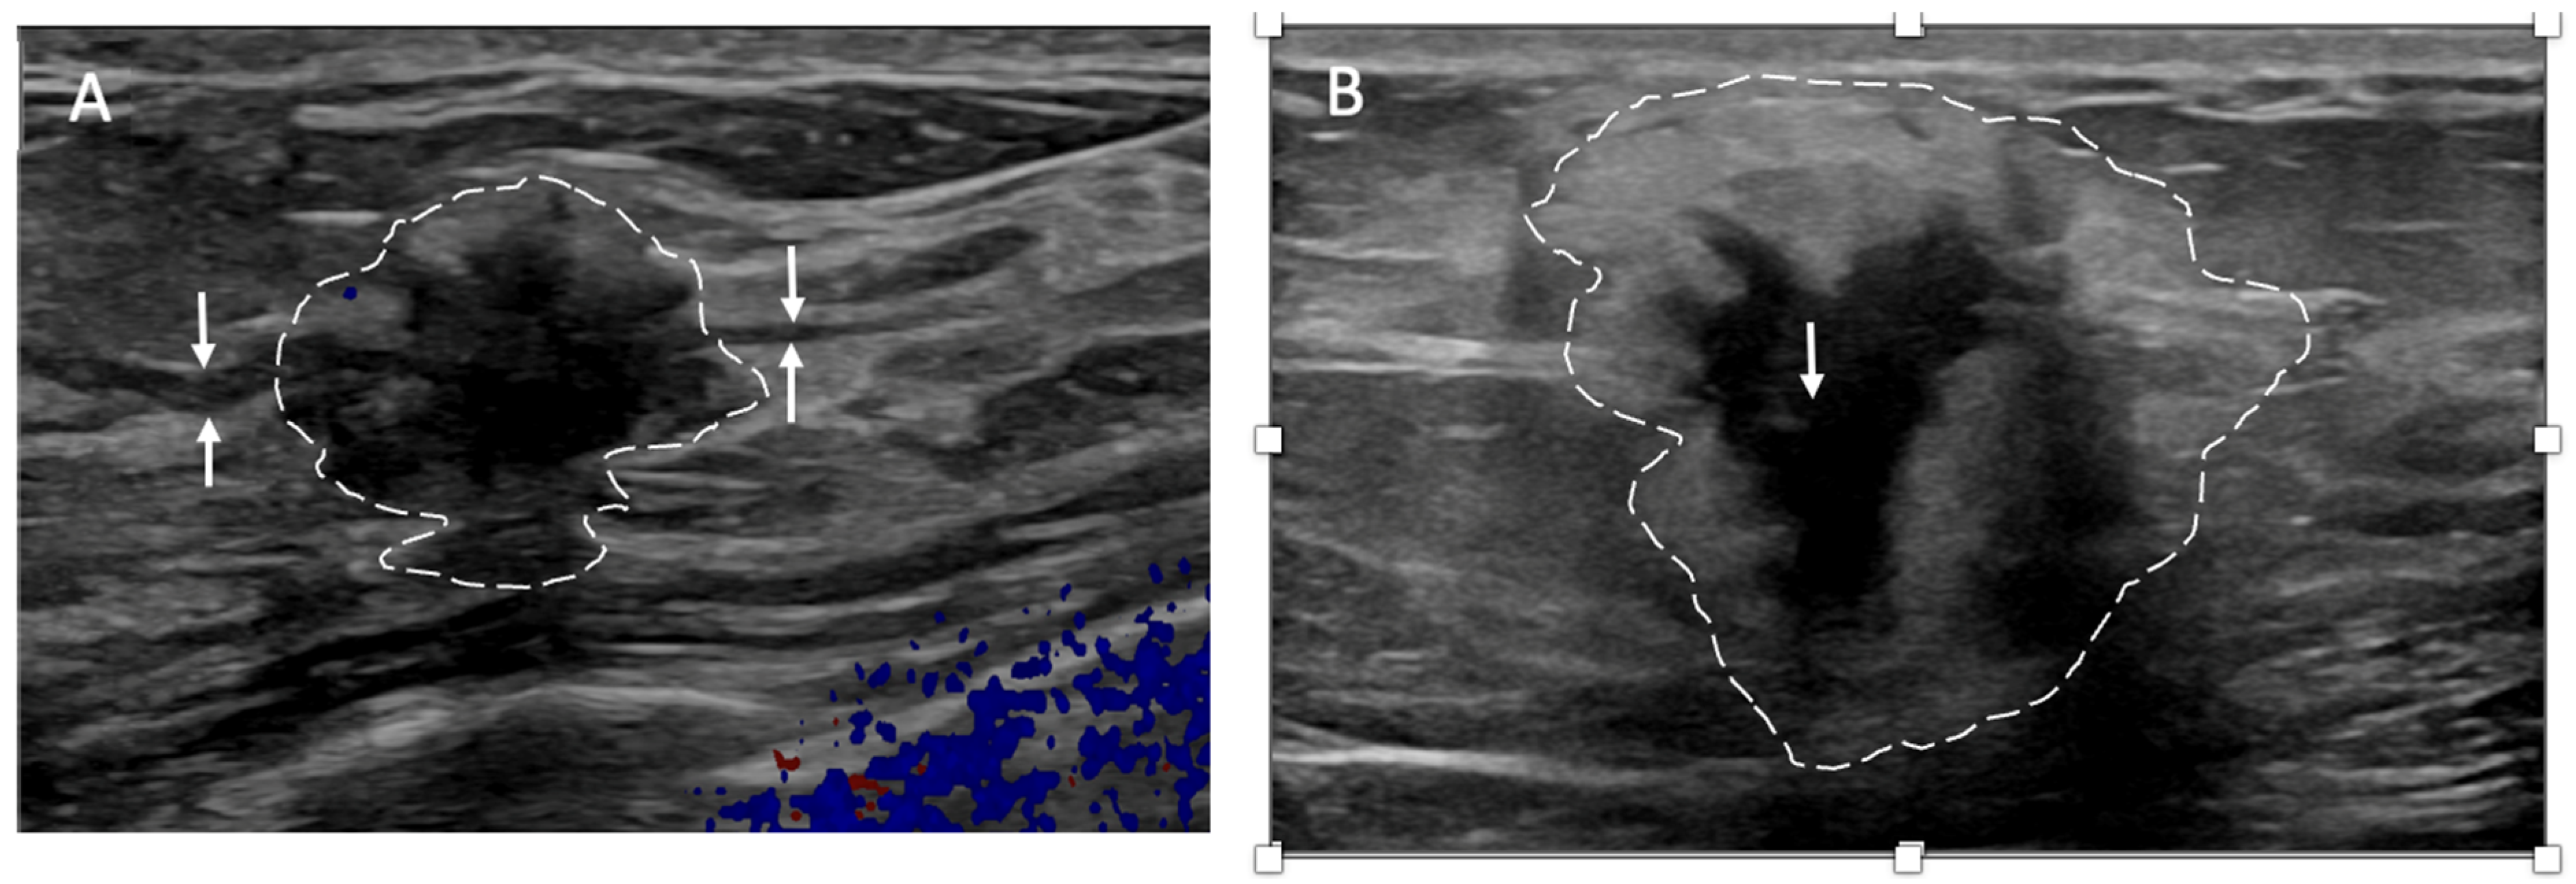

Ultrasound of the breast. Office-based cryoablation is optimized for treatment of ultrasound-visible breast cancers. Consequently, breast ultrasound should be performed of all suspicious imaging abnormalities to assess eligibility for ultrasound-guided cryoablation. Ultrasound permits assessment of the cancer’s proximity to the overlying skin and underlying chest wall and also enables detection of changes in adjacent tissue architecture (e.g., edema, tissue distortion, extension of tumor into adjacent ducts) and could indicate the presence of more extensive disease that would need to be incorporated into the treatment plan (Figure 2). Proximity (<5 mm) of a cancer to the skin is generally regarded as a contraindication to cryoablation, but a safe skin distance can sometimes be created using hydrodissection or injection of saline between the tumor and overlying dermis.

Figure 2.

(A) shows dark, dominant, irregular mass encircled by hash marks with intraductal tumor extensions (dark bands bracketed by paired arrows) extending from left and right sides of dominant mass. (B) shows dark, irregular dominant mass (arrow) surrounded by peri-tumoral edema outlined by hash marks.

Ultrasound of the axilla. Axillary ultrasound permits the detection of abnormal appearing lymph nodes that might not be detected on physical examination, mammography, or breast MRI. Axillary ultrasound is the most sensitive imaging study for the detection of subtle changes in the shape or thickness of a lymph node cortex that might indicate the presence of lymph node metastasis (Figure 3). Detection of suspicious lymph nodes determines clinical cancer stage and requires a specific plan to manage the possibility of lymph node metastasis.

Figure 3.

Hash marks outline abnormal appearing axillary lymph node measuring 1.5 cm in maximal diameter. Paired “+” marks indicate the span of a 0.4 cm area of focal cortical thickening that is suspicious for a metastatic deposit within the lymph node.